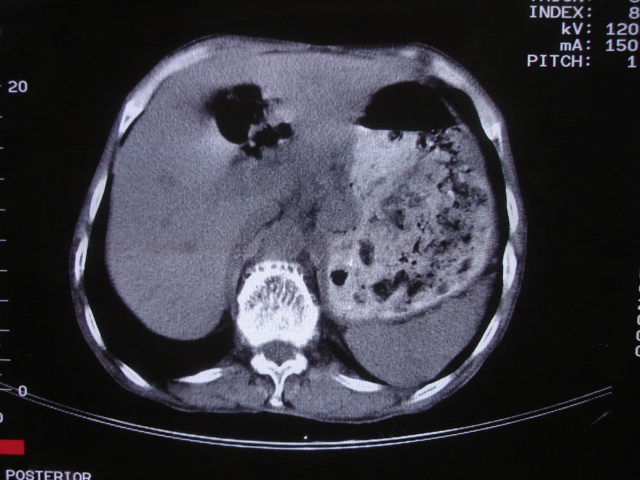

以下是引用深泽交通医院在2008-7-17 12:39:00的发言:[br]胃下垂;胃窦占位